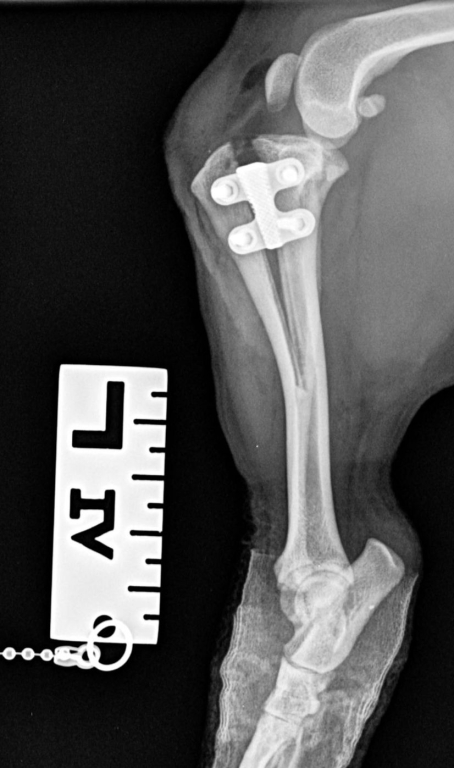

New research led by Orthopaedic Specialist Steve Butterworth at CVS’ Weighbridge Referral Centre, Swansea has found that tibial tuberosity advancement (TTA)-Rapid, a popular technique to treat cruciate ligament rupture in dogs, offers a good medium to long-term treatment outcome for canine cranial cruciate ligament failure - even in patients with tibial plateau angles of greater than 30⁰.

TTA is a popular surgical procedure to treat dogs showing lameness associated with CCLI. Though past research has highlighted satisfactory short (6-12 weeks)[ii] and medium (mean 16 months)[iii] term outcomes, there is limited research on a longer (>16 months) follow-up periods. It has also been speculated that dogs with tibial plateau angles (TPA) of greater than 30⁰ are not well suited for a TTA[iv].

The researchers reviewed patient records for a total of 149 TTA-Rapid procedures carried out in 120 dogs over an 80 month period. They also reviewed owner questionnaires that evaluated the outcome of at least six months after surgery, using a validated clinical metrology instrument, Liverpool Osteoarthritis in Dogs (LOAD). Follow-up questionnaires were received from owners of 64 of the 120 dogs (53.3%), with a median follow-up time of 37.5 months. This cohort included a wide range of breeds, aged between 2&12 years and with bodyweights ranging from 6.3 to 41.8kg. The dogs included 37 females and 27 males, and of the 79 limbs treated in these dogs, 41 were left and 38 were right. The researchers found 26 of the dogs (40.6%) had a TTA performed with a TPA less than 30◦ and 38 (59.4%) with a TPA of 30◦ or more. Of the 79 procedures, meniscal injury was noted in 27 (34.2%), surgery to stabilise the patella was required in 11 (13.9%), there was one surgical site infection (treated successfully with a short course of antibiotics), one dog sustained a fracture of the tibial seven days after surgery, and one sustained a late meniscal tear 12 months after initial surgery (treated successfully by partial meniscectomy).

The outcome was judged to be satisfactory, based on frequency of lameness, in 63 (98.4%), while satisfactory outcomes were achieved in 61 (95.3%) based on severity of lameness and in 50 (78.1%) based on mobility score. Statistical analysis showed that age, bodyweight, tibial plateau angle (TPA), meniscal injury, and concurrent patellar surgery did not influence the outcome, but time to follow-up positively correlated with mobility score (suggesting mobility declined with time from surgery).

The researchers concluded that the long-term (median of 37.5 months) outcome for dogs undergoing TTA-Rapid for cranial cruciate ligament disease is satisfactory, with no risk factors associated with poorer outcomes identified. Their study also revealed no evidence to support the suggestion that dogs with TPAs of greater than 30◦ may be inappropriate candidates for TTA - after testing several parameters to judge outcome including frequency of lameness, severity of lameness, distance walked daily and mobility score.